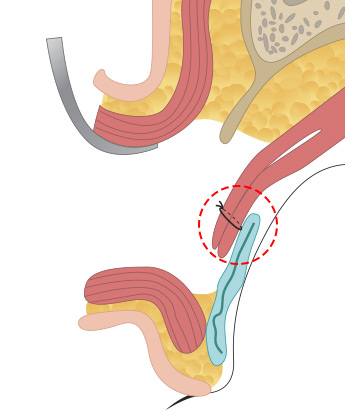

근육과 근막이 안검판이라는 조직에 붙어 있는데 안검하수의 정도에 따라서 경미한 경우는 근막의 길이를 축소해서 다시 붙여주는 상안검거근막 수술을 해주고, <br>

중증도의 경우 뮬러 근육을 당겨서 안검판에 고정하는 수술을 하고 중증인 경우에는 상안검거근을 아래로 당겨서 축소해주는 수술을 합니다.

올림근 널힘줄 중첩술

올림근 널힘줄 중첩술

올림근 널힘줄 중첩술 -

뮬러근 중첩술

뮬러근 중첩술 -

뮬러근 전진술

뮬러근 전진술 -

뮬러근과 올림근, 널힘줄을

뮬러근과 올림근, 널힘줄을

동시에 전진술로 교정